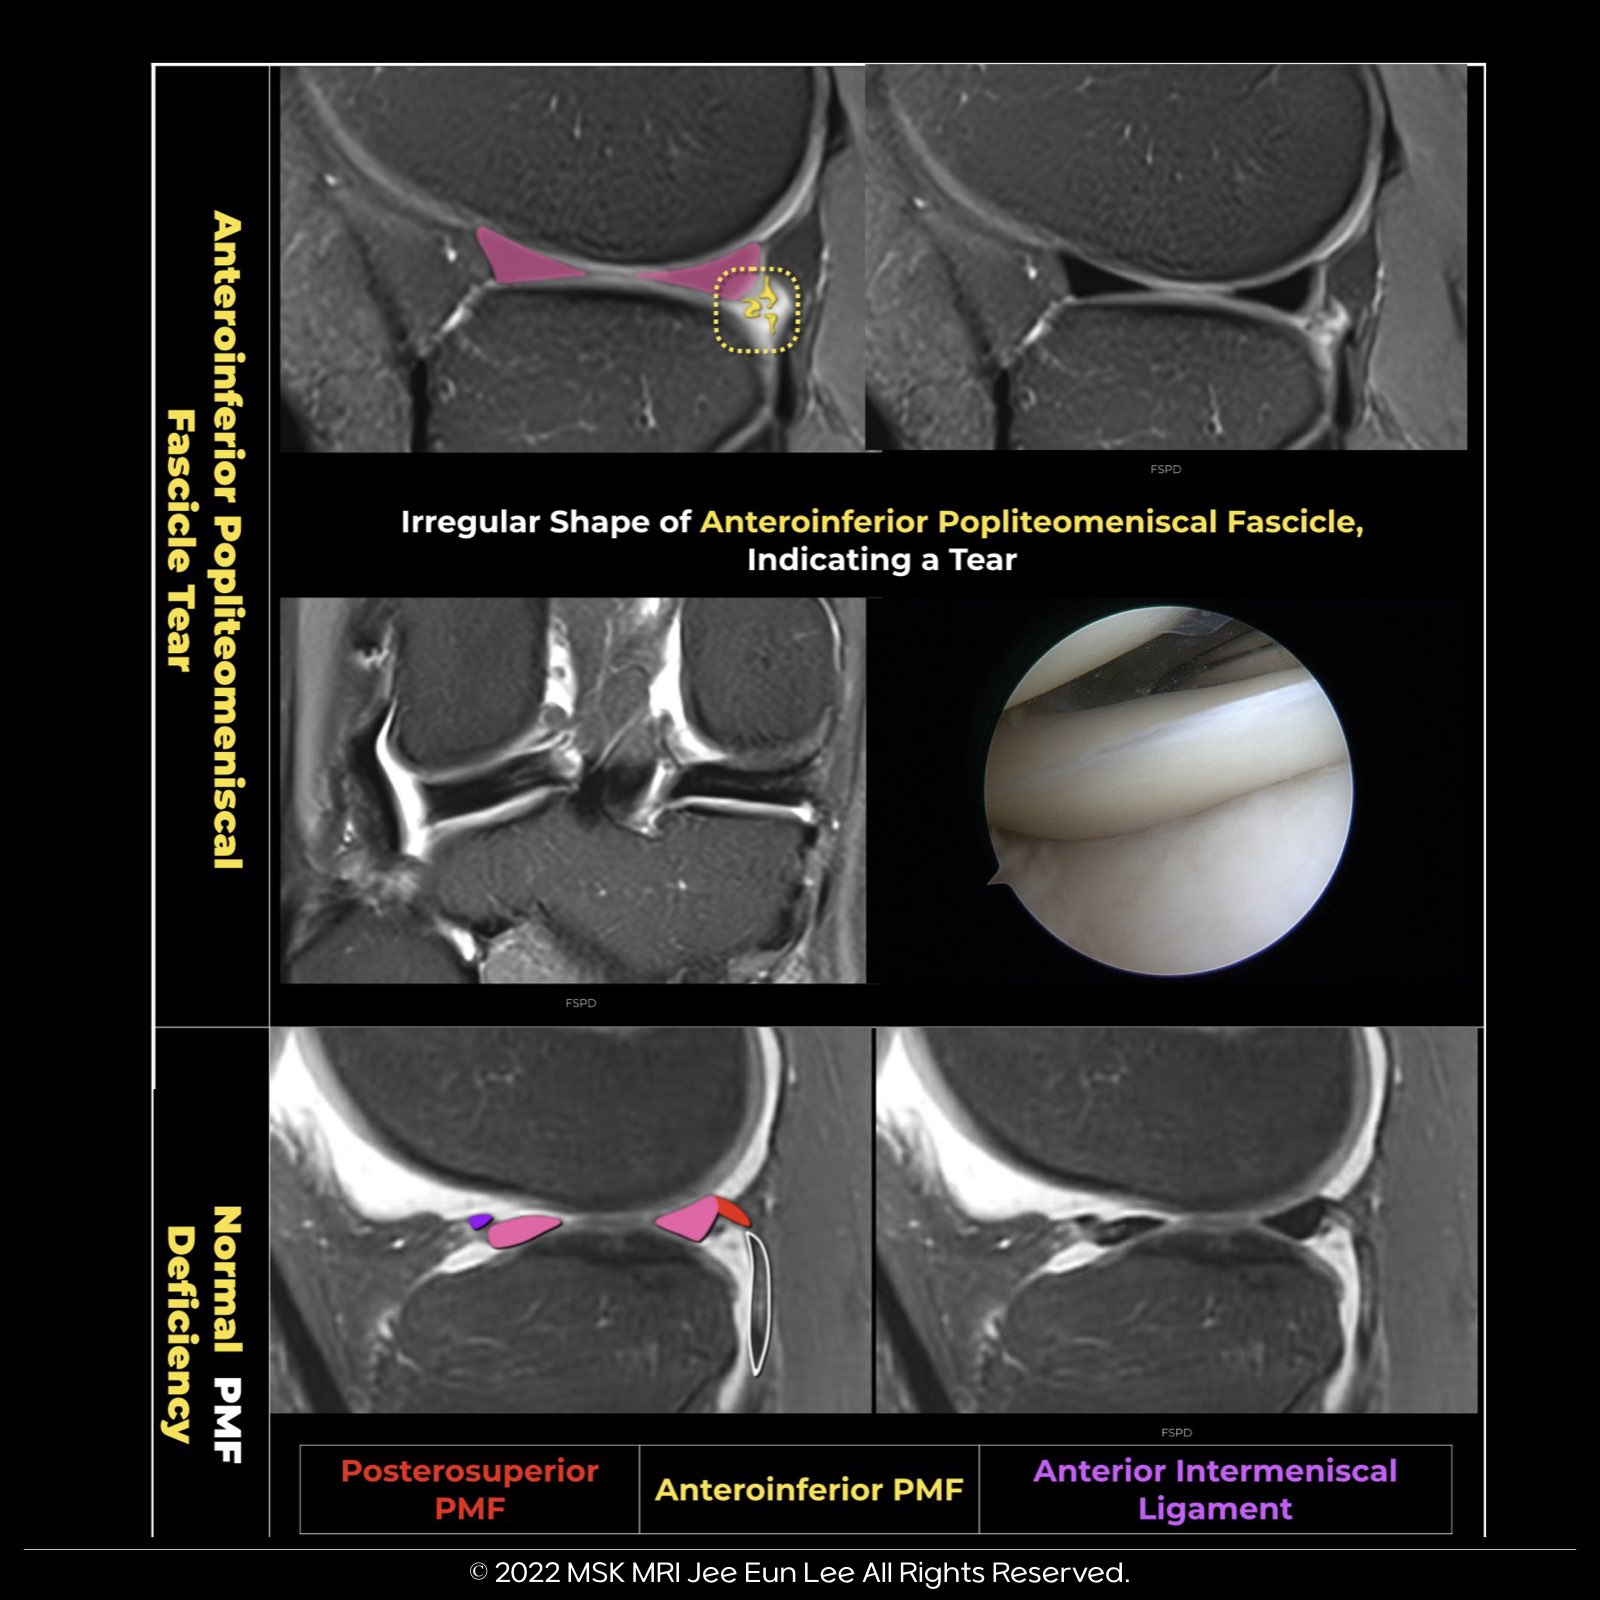

🔵🇰🇷Tear of popliteomeniscal fascicles

- When assessing a knee for a hypermobile lateral meniscus (LM), it's important for the radiologist to concentrate on the anteroinferior and posterosuperior popliteomeniscal fascicles (PMFs).

- This is because a total rupture or lack of these structures correlates with a significantly higher likelihood (with odds ratios of 12 and 6, respectively) of a hypermobile LM.

- Despite some controversy, there are surgeons who advocate for repairing all instances of symptomatic LM instability when an MRI and arthroscopy confirm a PMF tear.

Radiographics. 2023 Jul;43(7):e220208.